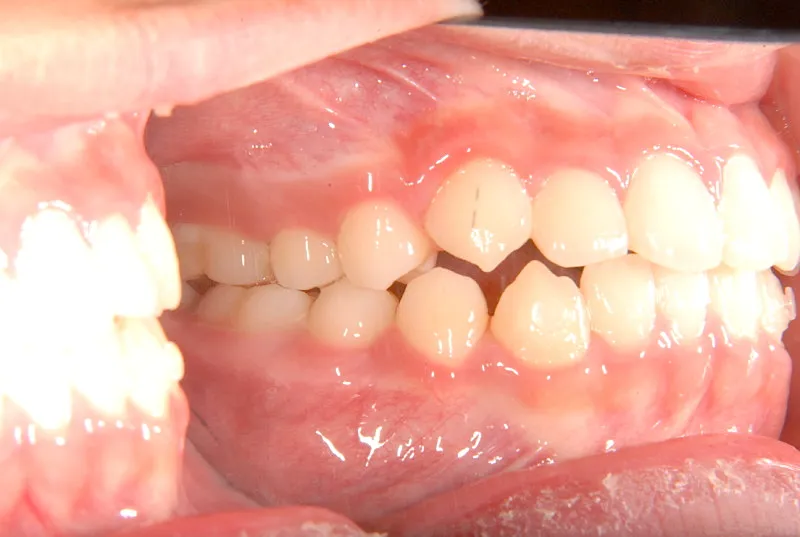

初診時年齢 小学校2年生 (男性) 主訴 癒合歯・永久歯が生えるスペースがない

診断名 叢生 装置名

上下の歯並びが狭く、永久歯の生える隙間がありません。

右下に癒合歯があり 上下の歯並びのアーチが悪くなっています。